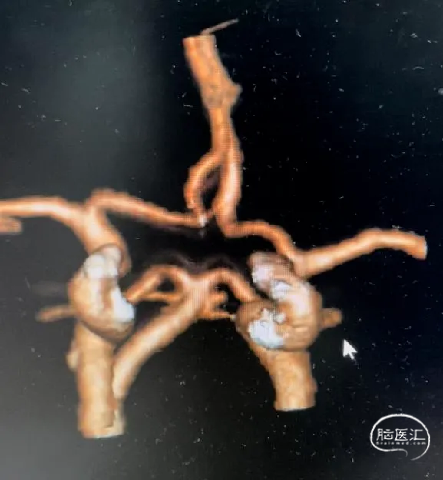

术前影像

栓塞过程

Presgo®微导丝引导支架微导管于基底动脉末端,并预留支架。陆续填塞Jasper®SS弹簧圈4枚,瘤腔填塞致密,撤出支架系统。

术后即刻影像

本病例是基底动脉末端的微小动脉瘤,治疗难度高,适合首选介入栓塞治疗。选择使用加奇Presgo®微导丝、微导管及Jasper®SS弹簧圈,填塞过程顺利,Jasper®SS弹簧圈的柔软性、顺应性表现良好,未见明显踢管现象,电解脱快速顺利。